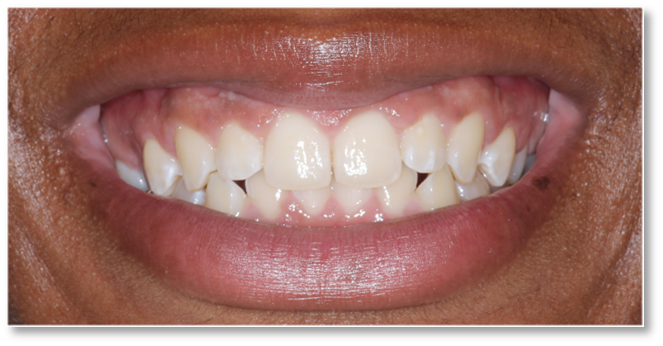

Before and after Periodontal Therapy

Advanced Gum Care: Non-Surgical & Surgical Options Available